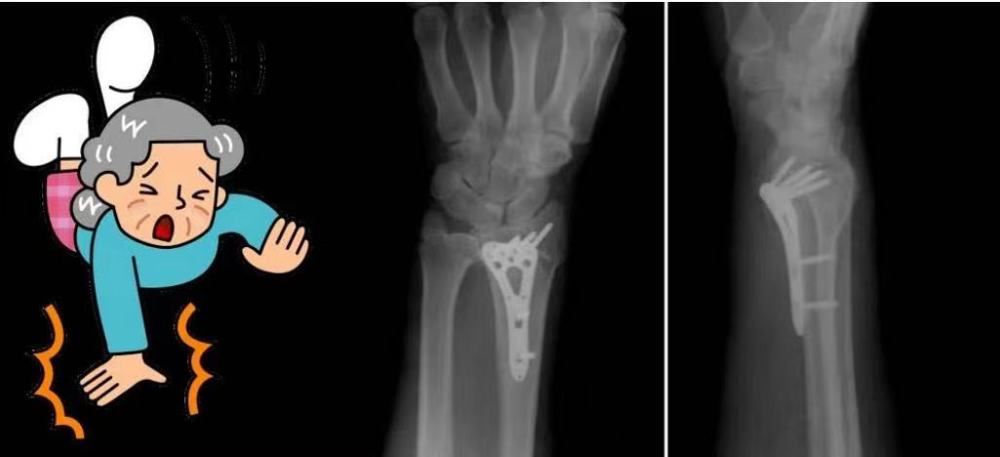

2. 桡骨远端骨折

生活中,我们常目睹这样的一幕:老年人不慎摔倒的瞬间,手臂总会下意识的撑扶身体,而就是这样一个下意识自我保护的动作,非常容易导致“桡骨远端骨折”。

桡骨远端骨折是指腕关节以上3厘米以内的骨折。该处是松质骨与密质骨交界处,本身就很容易发生骨折,再加上老年人骨质疏松,骨强度严重下降,摔倒后反应速度慢,不能及时调整体位,导致整个体重集中作用于腕部而导致骨折。

一旦发生这种情况,不可自行对手腕部进行揉捏,以免加重损伤。可适当局部冷敷,用夹板固定或用丝巾悬吊在胸前,既减轻了疼痛,又起到了临时固定的作用,并迅速到医院进行诊治。